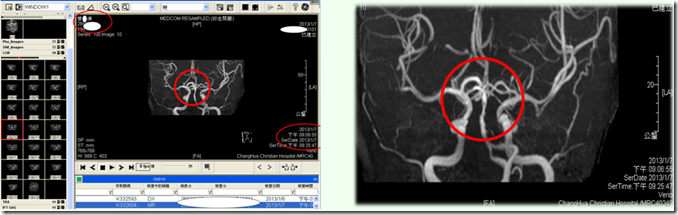

2013.01.07(一)血液、尿液检查, 8:53pm医院安排曾先生进行MRI核磁共振,诊断确认为梗塞性脑中风。

MRI核磁共振影像显示,实体白色区段为血管堵塞处。